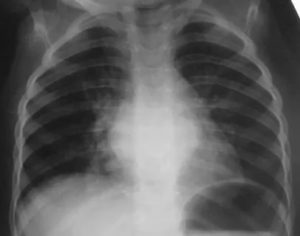

Как выглядит бронхит на рентгеновском снимке

Рентгенограмма – это дополнительный способ обследовать органы системы дыхания. Она даёт возможность сделать диагностику или исключить возможность пневмонии, обструкции, туберкулёза, онкологии. Излучённые лучи от рентгенаппарата не воспроизводят и не воссоздают изображение бронх на кадре.

На снимке можно различить всего лишь побочные признаки заболевания. Диагностировать воспаление бронхов по рентгенограмме нельзя. Если только отсутствуют патологии лёгочного заболевания, то признаки относят к бронхиальному недугу. На рентгеноскопии снимочные кадры показывают любой орган разнообразно.

Рентген лёгких показывает пятна разнообразной яркости, если существует отклонение. Цвет пятен на лёгких тёмный, это свидетельствует о воспалительном процессе и отёчности.

Бронхит на рентгене не виден. Это связано с тем, что проникновение лучей через стенку и воздушное наполнение пазух бронх происходит свободно. В случае воспалительного процесса бронх на негативе видны тени в форме колец, значит у пациента протекает хронический процесс.

Бронхитная болезнь на снимочном кадре представляет собой:

1. Изменение лёгочного рисунка &#8212, капилляры мелкой формы, слегка заметны.

2. Очаговый спад ткани.

3. Чёткость корневой системы лёгкого теряется, заметно его увеличение.

4. Утолщённость стенок бронх.

5. Тканевой участок можно заметить без сосудов.

6. Инфильтраты чётко проглядываются.

7. Изображения контуров нечёткие.

8. Нижний лёгочный канал купируется пузырьками светлого оттенка.

Врач рентгенолог описывает присутствие отёчности лёгочного органа, наличие рубцовой ткани или деформацию бронхов. Бронхит на снимке рентгена не показывается, а только просматривается диффузионная изменчивость тканей, раскрываются форменные отклонения и наличие содержимого в органах дыхания.